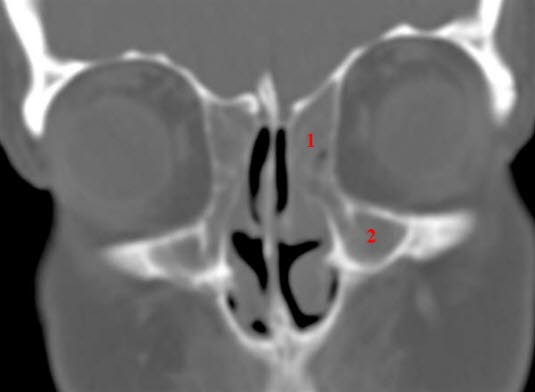

Zablokowana zatoka szczękowa i zatoka czołowa, zapalenie zatok, TK

- TK (niska dawka) i stożkowa tomografia komputerowa (Cone Beam Computed Tomography – CBCT)

- zapewniają najlepszą wizualizację zatok przynosowych.